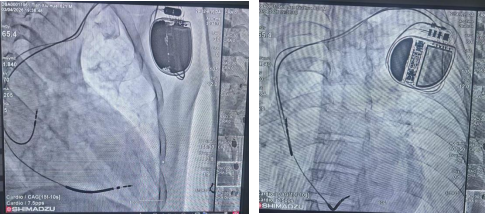

植入双腔ICD后手术图像

经该院心血管内科团队全面评估,决定为其植入双腔ICD,其可同时感知起搏心房与心室,维持房室协调收缩,对改善患者远期心功能和生活质量意义重大。